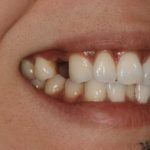

Corey E.

This patient had lost his front tooth due to an accident and had an Implant placed to replace it.